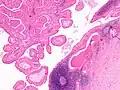

The appearance of this tumor under the microscope is unique. There are cystic spaces surrounded by two uniform rows of oncocytes, which are epithelial cells with abundant, granular, eosinophilic cytoplasm.[7] The cystic spaces have epithelium referred to as papillary infoldings that protrude into them. Additionally, the epithelium has lymphoid stroma with germinal center formation.

This Warthin's tumor presented as a parotid mass in a middle-aged male, who underwent superficial parotidectomy. The tumor, at the right of the image, is well-demarcated from the adjacent parotid tissue and tends to shell out from it.

Low magnification micrograph of a Warthin tumor arising from the parotid gland.

Histopathology of Warthin tumor in the parotid gland. H&E stain.